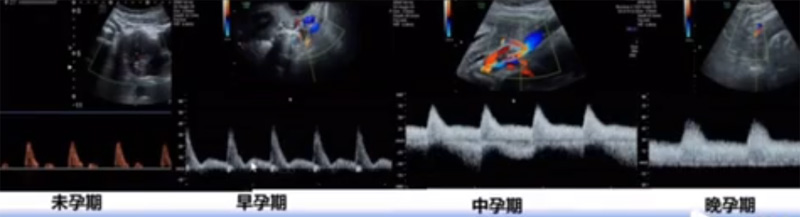

位于輸卵管的后下方,子宮兩側的后上方;借卵巢系膜與子宮闊韌帶后層相連。正常成人卵巢約4x3x2cm,跟睪丸的數值差不多,都是性器官,絕經后卵巢萎縮變小、變硬。所以絕經后婦女很難找到卵巢,主要功能:生殖和內分泌功能分泌性激素。女性的第二性征。女性內生殖器的血管分布,動脈有子宮動脈,卵巢動脈,陰道動脈,陰部內動脈。靜脈它是與動脈伴行。重要了解的是子宮動脈,子宮動脈是髂內動脈前干的重要分支,妊娠時候血流速度會增加的,為無創性檢查胎盤血管阻力的方法。未孕期頻譜為高阻力低舒張波形;正常妊娠時血流速度增加,血流阻力下降。